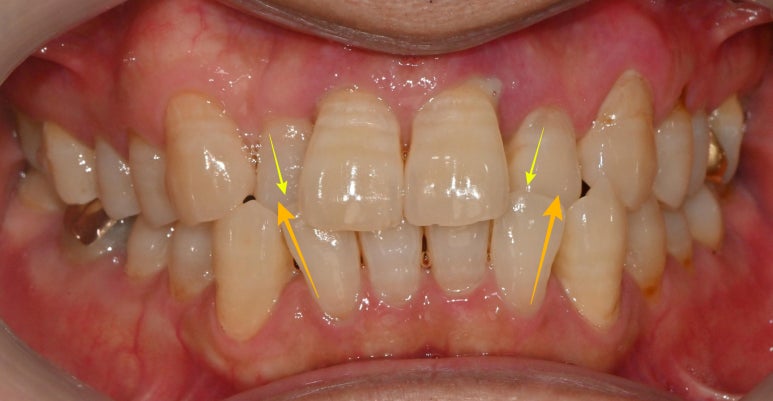

우선 윗니가 아랫니의 1/3을 덮어야

바람직한 교합관계인데,

이 케이스에서는 양측 윗니의 두 번째인

상악 측절치가 안으로 들어가

아래 앞니 두 번째와 반대로 자리하고 있습니다.

그렇기 때문에

위아래 치열이 틀어져

심미성도 떨어지고

평소 치태나 구강관리에도

어려움이 있으셨을듯합니다.